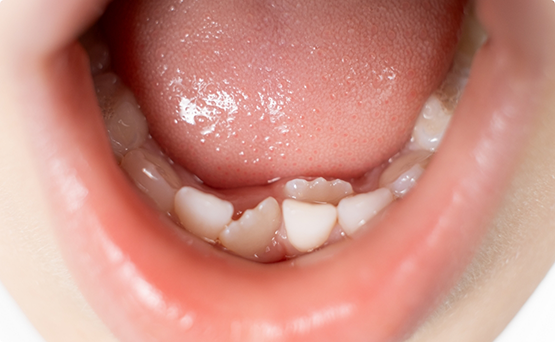

Crowded Teeth

Teeth that are too close together can be difficult to clean, leading to an increased risk of decay. Invisalign, along with other treatments (such as the extraction of teeth), can relieve the crowding of your teeth.